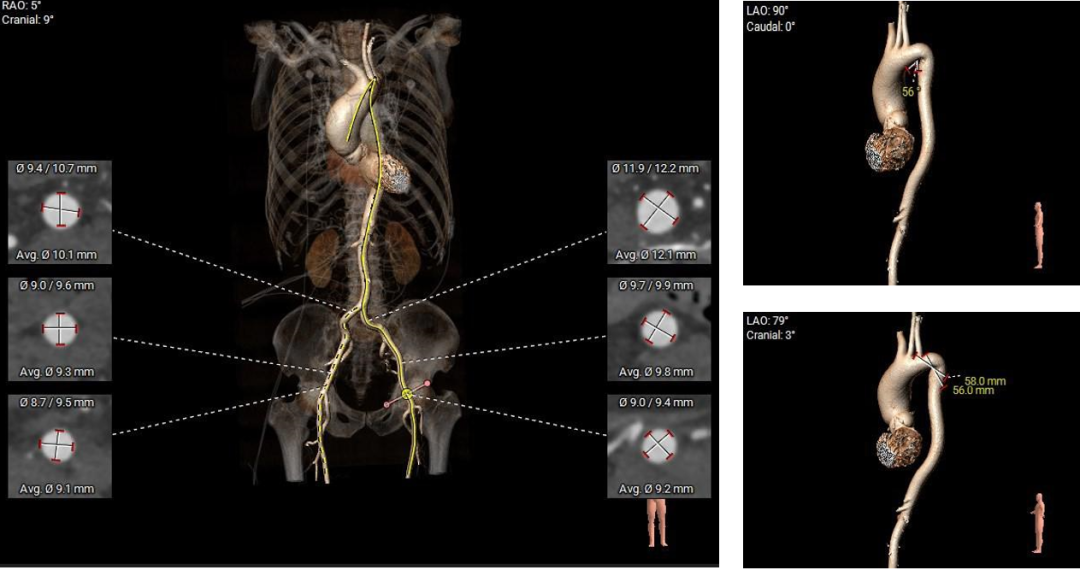

1.主动脉瓣瓣环周长83.8mm,平均周长径26.7mm。

2. Type0型二叶式主动脉瓣,左右冠不同窦,瓣叶中度钙化伴增厚,钙化分布不均匀,主要分布于瓣叶对合缘处。

3. 左右冠开口高度可,左冠瓣叶长度<瓣叶附着缘到冠脉开口处,右冠瓣叶长度>瓣叶附着缘到冠脉开口处,瓦氏窦、窦管交界内径尚可,升主动脉瘤样性扩张(最大直径52.2mm) 。

4. 流出道呈敞口型,心室腔偏大 。

5. 瓣环水平夹角45°,非横位心,主动脉弓距偏短,夹角偏锐。

6. 双侧髂动脉走行尚可,股动脉穿刺区域未见明显钙化斑块,整体血管入路直径良好。

外周血管及主动脉弓解剖: